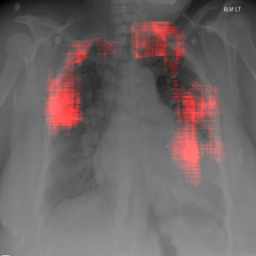

4.2.1 Cardiomegaly Localization

The localization of abnormalities in cardiomegaly examples are shown in Fig. 7. Here, of the image area is shown which has the highest sensitivity. It can be observed from the figures that the network is indeed most sensitive to the region where the heart is larger than a normal heart. We have performed this experiment on cardiomegaly and normal images and found this localization to be consistent for most examples. There is not much functional difference between a normal and cardiomegaly example other than the fact that the heart in cardiomegaly is larger than a normal heart. Given the fact that the normal images could also have various size of heart depending on the age or physical attributes of a patient, we found this level of localization sensitivity to be remarkable. Also interesting is the fact that the standard rule based features like CTR and CTAR take into account the relative size of heart and lung to determine if there is cardiomegaly present or not. In the DCN localization experiment, we see counter-intuitively that most of the signals contributing to the softmax score are coming from the heart only. This means that there are characteristic features in the shape of the heart and its surrounding regions that alone is sufficient to detect cardiomegaly. The lung and its relative size are probably less important features when trying to detect cardiomegaly. This observation is counterintuitive and needs to be explored further in future work.

8 Additional Examples of Localization

In this section we show more examples of localization. Few localization samples are shown in Fig. 11. It can be observed that, in the CXRs with Cardiomegaly (Fig. 11(a) and (b)) a fine localization around the heart is observed. In the normal CXRs (Fig. 11(c) and (d)) such localization is not observed. Rather the lowest probabilities are spread out in the CXR image. It is interesting to note that, the localization algorithm gets low probability where the heart is enlarged during cardiomegaly, but the proportion is small compared to the localization in other areas of normal CXRs. In order to observe the performance of the heat map we computed histograms of heat maps of each of the 100 CXRs in the test set for Cardiomegaly detection and average histograms are shown in Fig. 11(e) and (f) for CXRs with Cardiomegaly and normal CXRs, respectively. It is to be noted that, the histograms include both success and failure cases. It can be observed that, for CXRs with Cardiomegaly the classifier is highly sensitive toward Cardiomegaly detection even under occlusion. This indicates that, the classifier primarily looks for local features in a CXR instead of some feature that is spread out in the entire CXR. However, the classifier is not sensitive toward normal CXRs under occlusion. Rather, the probabilities are spread out in the probability spectrum. After that, we analyzed the failure cases where the classifier is unable to classify the image correctly. Two such examples of failure cases are shown in Fig. 12. The localized CXR shown in Fig. 12(a) contains Cardiomegaly whereas the classifier detects it as normal. However, the localization shows that it localizes around heart quite well despite the in accurate classification. On the other hand, Fig. 12(b) shows an example of normal image which has been classified as Cardiomegaly by the classifier. There is stronger localization around the hear that that is observed for normal images as in Fig. 11(c) and (d), however, like those images the localization is spread out.